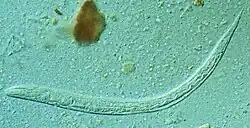

Une larve de Strongyloides stercoralis.

L'anguillule parasite de l'intestin est une minuscule femelle parthénogénétique strongyloïde, très mince et longue de 2 à mm. D'autres formes adultes, mâles et femelles stercoraux (qui concernent les excréments) existent seulement à l'état libre ; elles sont rhabditoïdes et atteignent mm pour la femelle, un peu moins pour le mâle.